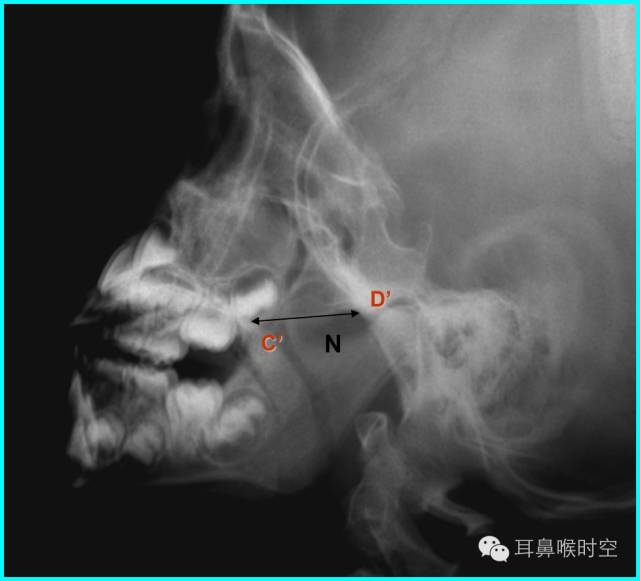

鼻咽侧位片的测量方法(二)

腺样体-鼻咽腔比率A/N值:

(1)1987年Elwany提出鼻咽腔的宽度(N)测量方法:

硬腭后端至翼板与颅底交点间的距离为鼻咽腔的宽度。

(2)现多用的鼻咽腔的宽度(N)测量方法:

N为腺样体最凸部鼻咽腔的宽度,即垂线的反向延长线与硬腭后端或软腭前中部上缘的交点和枕骨斜坡颅外面切线的垂直距离。

根据经典Fujioka 等 X 线平片测量法原理:

A/ N 比:测量腺样体最大厚度与自硬腭上缘到颅底蝶枕骨的软骨结合部的距离之比

PAS:后气道间隙(pharyngealairway space , PAS)的宽度(软腭表面与腺样体表面之间有效气道宽度)。

N 线:即从蝶骨体2枕骨斜坡的软骨结合部后缘(O点)至硬腭与软腭上缘交界处的连线N

A 线:过O点沿枕骨斜坡下缘作延长线L,取腺样体下缘最凸点作L线的垂直线。

A/N比:分别测A、N值,计算A/N 比